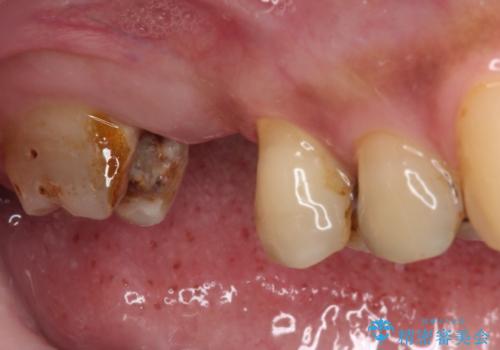

- 詰め物が外れたまま放置してしまったとのことで来院された患者様です。

詰め物が外れた部分は虫歯が進行しており、周辺には歯石が付着している状態でした。

1歯欠損していたため、オールセラミックブリッジによる補綴治療を行うこととしました。